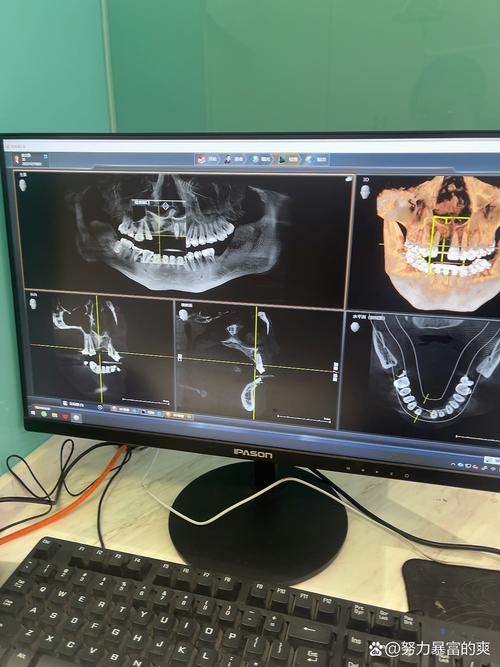

我种的牙用了三年多,从最初的忐忑不安到现在的习以为常,这段经历让我对“牙齿”有了全新的认识,缺牙那几年,我总感觉吃饭不香,连笑都小心翼翼,生怕露出牙缝里的尴尬,后来下定决心种牙,从拍CT、植入种植体到戴上牙冠,整个过程像是一场和牙齿的“重生之旅”,而如今,这颗牙早已成为我生活中不可或缺的一部分,每天陪我咀嚼美食、自信微笑。

骨结合期是最考验耐心的,医生说种植体要和牙槽骨长牢,大概需要3-6个月,这期间我拒绝了一切坚硬、黏牙的食物,连牛肉干都不敢碰,怕给种植体带来过大的咬合力,有天朋友约吃火锅,看着别人嚼毛肚、嚼鸭血,我只能默默涮青菜,心里虽然馋,但想到“等牙根长结实了天天吃火锅”,也就忍了。

医生还提醒我,要关注全身健康,我有轻度牙周炎,以前定期洗牙,现在洗牙时会特别告诉医生“这里有种植牙”,医生会用更温和的器械清理,避免损伤种植体,如果血糖不稳定(我是糖尿病患者),也会先控制血糖再处理牙齿问题,因为高血糖会影响骨结合,甚至导致种植体松动。